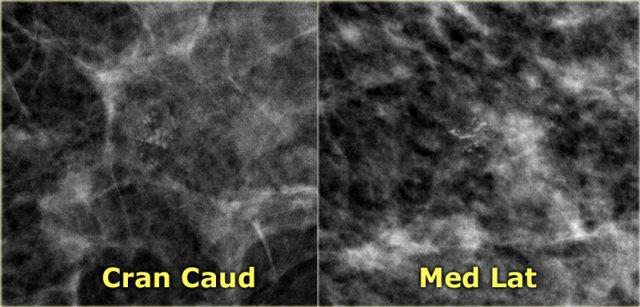

Cụm vôi hóa trên tư thế MLO có cấu hình hoàn toàn giống với cụm trên tư thế CC (hình tiếp theo).

Trên tư thế CC, cấu hình của các vi vôi hóa hoàn toàn giống nhau.

Nếu các vôi hóa này nằm ở trung tâm vú, chúng phải có cấu hình khác nhau vì góc chiếu khác nhau.

Chỉ khi vôi hóa nằm trong da thì cấu hình của chúng mới giữ nguyên.